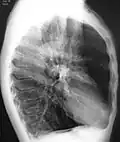

A chest X-ray is not useful to establish a diagnosis of COPD, but it is of use in either excluding other conditions or including comorbidities such as pulmonary fibrosis and bronchiectasis. Characteristic signs of COPD on X-ray include hyperinflation (shown by a flattened diaphragm and an increased retrosternal air space) and lung hyperlucency.[5] A saber-sheath trachea may also be shown that is indicative of COPD.[111]

Chest X-ray demonstrating severe COPD, displaying small heart size in comparison to the lungs